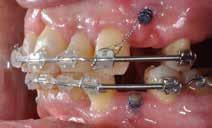

Ortodontisk behandling af patienter med parodontitis kan ofte foretages sikkert ved at følge en systematisk tilgang, der omfatter 1) inflammationskontrol, 2) ortodontisk korrektion og 3) livslang vedligeholdelse. Inden behandlingen påbegyndes, skal parodontiet generelt være sundt med pocher på maksimalt 4 mm og et plak- og blødningsindeks under 10 %. Restfæstet skal være tilstrækkeligt til at modstå behandlingen, som udføres med kontrollerede kraftsystemer. Målet er at forbedre æstetik og opnå normal funktion, som kan vedligeholdes på lang sigt samt facilitere restaurerende behandling.

Der planlægges alignerbehandling af begge kæber med intrusion af 1+1 og 2,1-1,2, nivellering af trangstilling UK med interproksimal reduktion (IPR) (Fig. 2 A, B) og senere IPR OK for reduktion af dark triangles mellem incisiverne efter nivellering. Patienten instrueres i at benytte alignere 20-22 timer/ dag med alignerskift hver 7. dag, og patienten ses hver 3.-8. uge under forløbet. Den første alignerserie består af 16 alignere for nivellering OK/UK og IPR i UK (Fig. 2). Efter denne serie planlægges IPR mellem incisiverne i OK for reduktion af dark triangles (Fig. 3) samt yderligere intrusion af OK og UK-fronten i 12 refinement-alignere. Patienten udviser god kooperation og er meget tilfreds med alignerapparaturet, som er mindre synligt end det faste apparatur (Fig. 4).

Behandlingen afsluttes med yderligere refinement-alignere for finindstilling af okklusionen, og efter 11 måneders ortodontisk behandling er der opnået normale relationer i alle tre